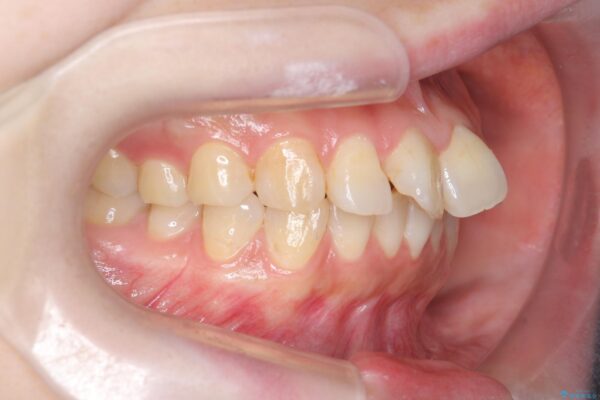

治療前

傾いた前歯、インビザラインで改善 治療前画像 傾いた前歯、インビザラインで改善 治療前画像 傾いた前歯、インビザラインで改善 治療前画像 傾いた前歯、インビザラインで改善 治療前画像